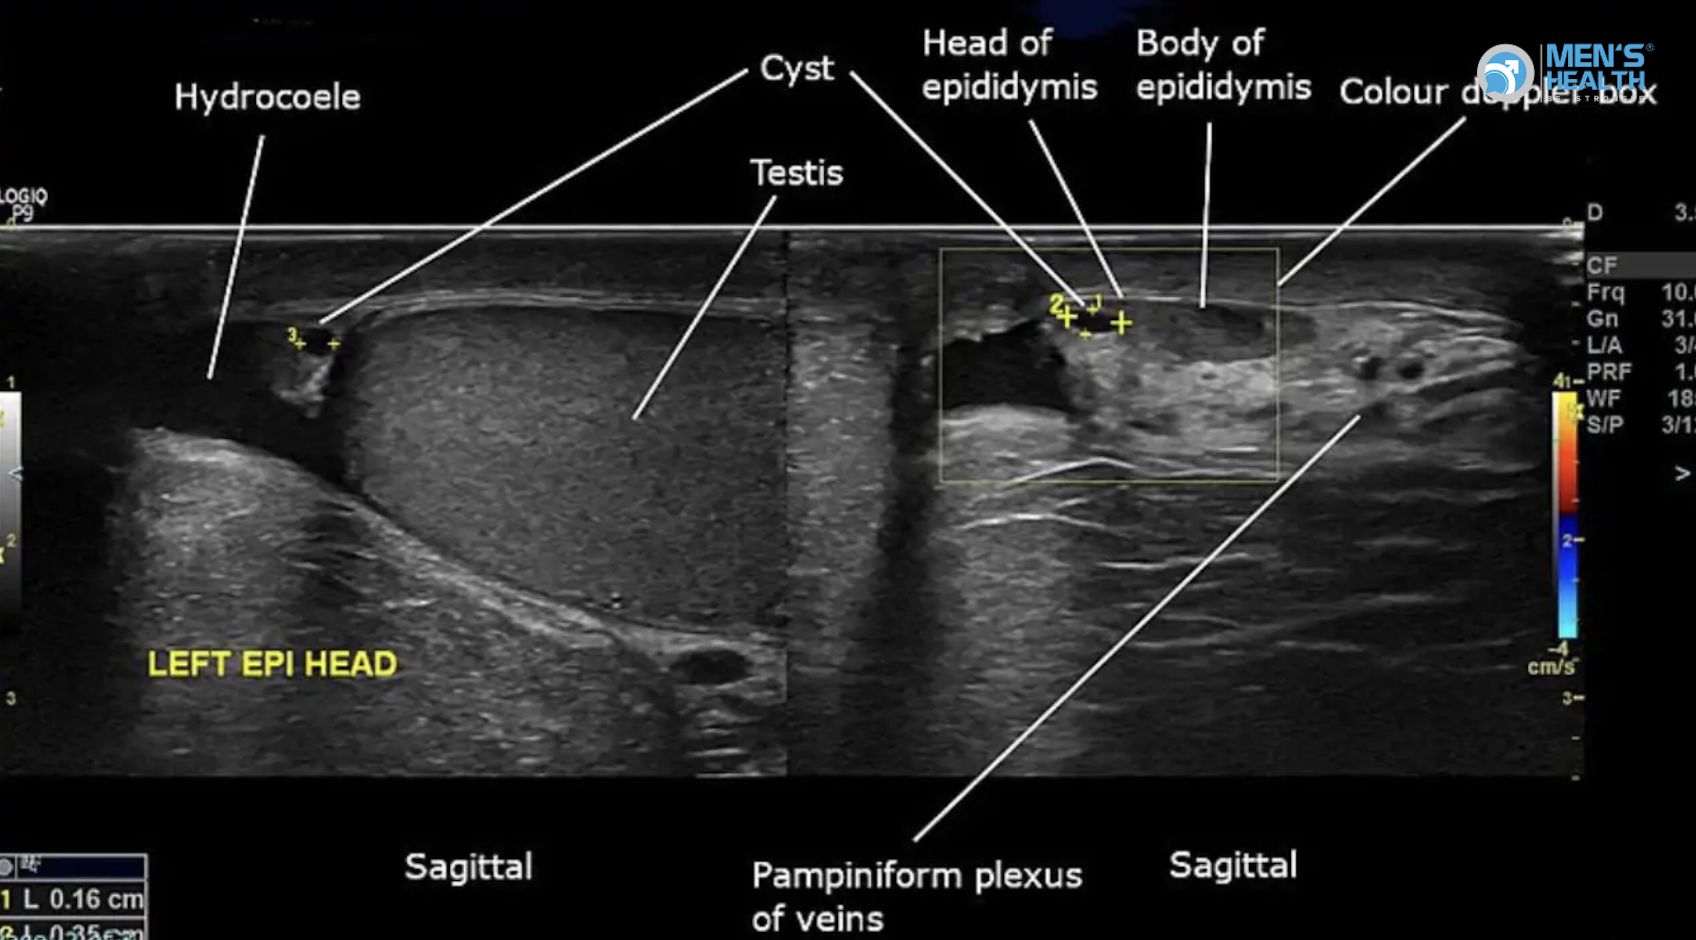

- Siêu âm Doppler: xơ hóa bao trắng thể hang, lưu lượng máu bình thường.

- Siêu âm: Vôi hóa nhẹ trong mảng xơ.